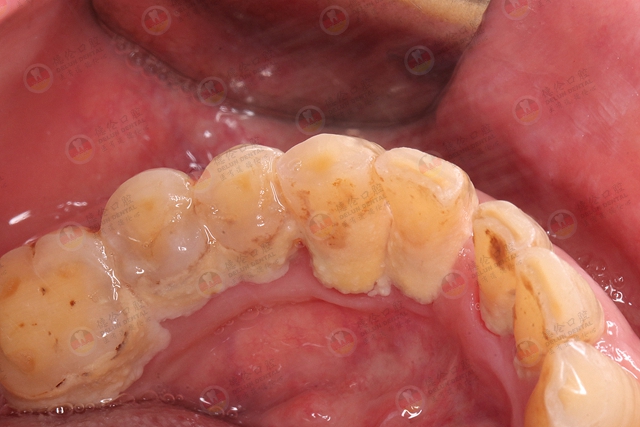

龈下结石,你口腔中的隐形炸弹!

牙龈老是肿胀,牙齿底部也有黑色脏东西,而且牙根都暴露出来,好像是牙龈萎缩,给医生检查的时候,医生却告知牙龈内有牙结石,奇怪了,牙结石难道都不是长在牙齿表面吗?

它不光是长在牙龈上面那些我们肉眼能看到的地方,在牙龈下面看不到的地方也长有牙结石。

众所周知,牙结石在牙龈上面可以看到,也比较容易清洁。如果是在牙龈下,那就说明你有牙周炎了,一般牙周袋通常比较深,经常藏污纳垢,菌斑堆积后形成牙结石,造成牙龈周围有发黑现象!

牙龈下面的牙结石肉眼看不到,一般呈褐色或者黑色,附着更坚固,而且牙结石易吸附细菌/毒素,再加上本身对牙周组织的刺激,会使牙龈内侧溃疡,不易愈合,导致牙龈出血,牙周疾病加重,口臭,牙周袋,牙齿松动甚至脱落等。